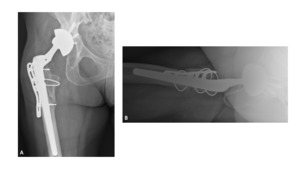

A 63-year-old female presented with recurrent THA instability - verbal consent was obtained for this report. She underwent L2-S1 posterior stabilization with L2-L3 anterior lumbar interbody fusion in May 2002 (Figure 1) and an uncomplicated right THA in April 2007. (Figures 2a-b) Five years following primary THA (July 2011), the patient sustained her first THA dislocation, which was treated with a closed reduction. Between 2011 and 2018, the patient had seven repeat episodes of hip instability – in 2012, one was complicated by a peri-prosthetic femur fracture requiring three revisions and reconstruction with a trochanteric claw plate. She was subsequently diagnosed with a prosthetic joint infection (PJI) which required an antibiotic spacer and subsequent re-implantation three months later. (Figures 3a-b) Following treatment of initial instability and femur fracture, the implants included a size 16 standard taper femoral stem and a 50-mm acetabular shell with 32-mm liner.